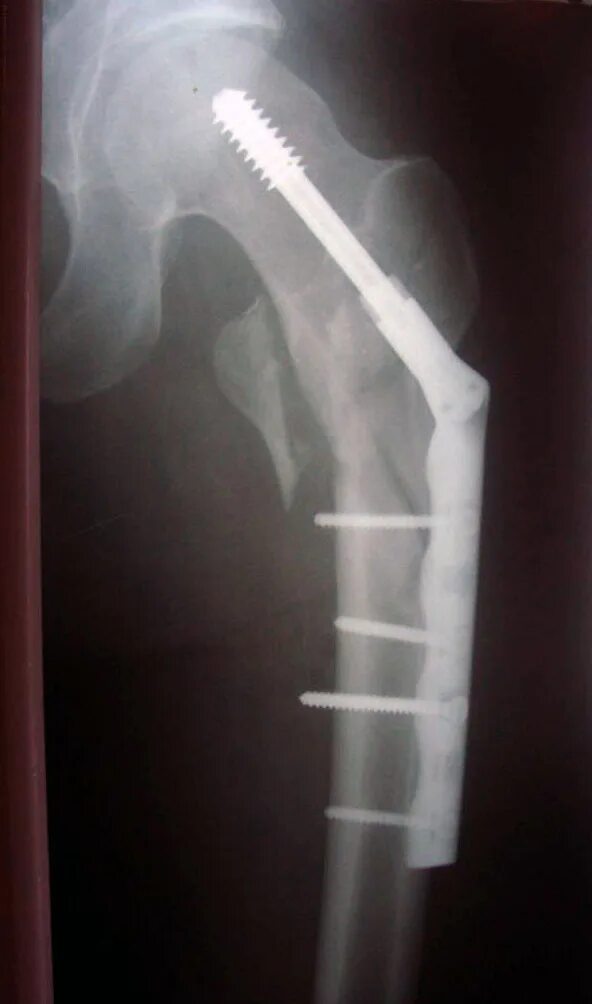

Почему не срастается